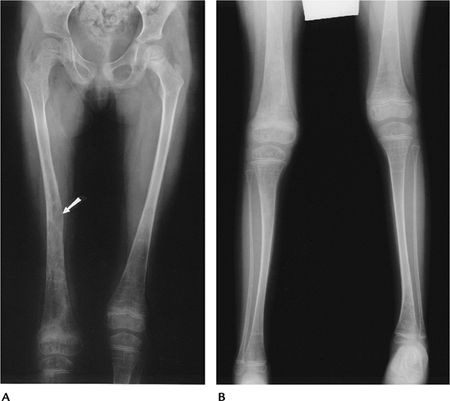

FIGURE 15-26 Osteogenesis imperfecta Type I (tarda). AP radiographs of the femora (A) and legs (B) showing thin, gracile osteoporotic bones with a healed fracture (arrow) in the right femur.